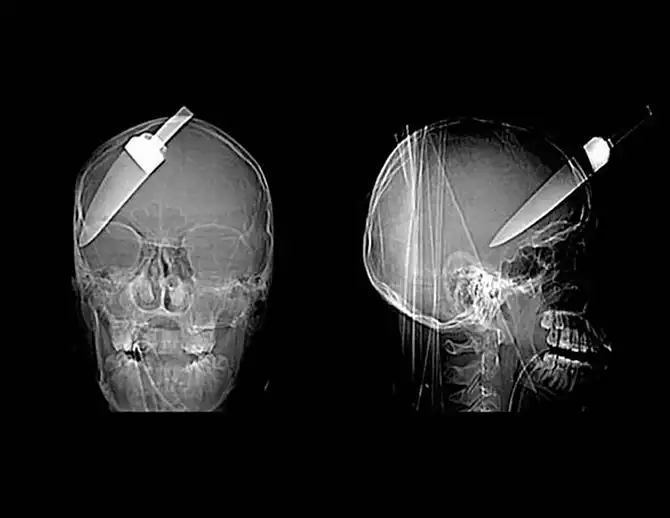

Копье от гарпуна, попавшее в голову 16-летнему мальчику на рыбалке.

Гвоздь в человеческом черепе – пациент случайно выстрелил в себя из пневматического молотка. Он даже не понял, что выстрелил в себя – 10-сантиметровый гвоздь обнаружили только через 6 дней.

Нож в голове 10-летнего мальчика. Мальчик выжил.

Граната в черепе заключенного.

12-сантиметровый нож в черепе подростка.